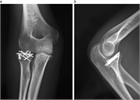

1. 橈骨頭骨折、橈骨頸部骨折の解剖学的特徴を把握する。

1. 橈骨頭骨折、橈骨頸部骨折は上腕骨小頭と橈骨頭が衝突して生じる。

1. 成人では橈骨頭に加え橈骨頚部も骨折しやすいが、小児では多くが橈骨頚部骨折である。